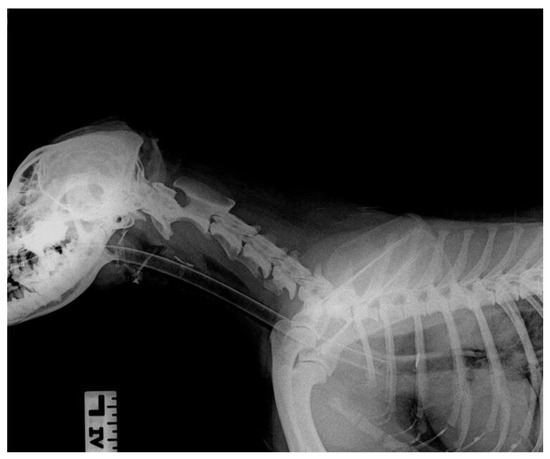

On physical examination, the dog demonstrated discomfort during the abdominal palpation. Otherwise, the dog was bright and alert, in a good condition, and had a body condition score (BCS) of 5 of 9 scale. The body temperature was 38.6 °C, the capillary refill time was <2 s, no cardiac or respiratory abnormalities were noticed during the auscultation, and no clinical dehydration was noticed. Complete blood count and biochemistry profile did not reveal any significant findings except for a slight increase in hematocrit, creatinine, and blood urea nitrogen. These findings indicate hemoconcentration, probably due to mild non-clinical dehydration (Table 1). Thoracic radiographs indicated an increased opacity in the esophagus and mild hepatomegaly (Figure 1).

Figure 1.

Lateral thoracic radiograph indicating increased opacity of the caudal portion of the esophagus.